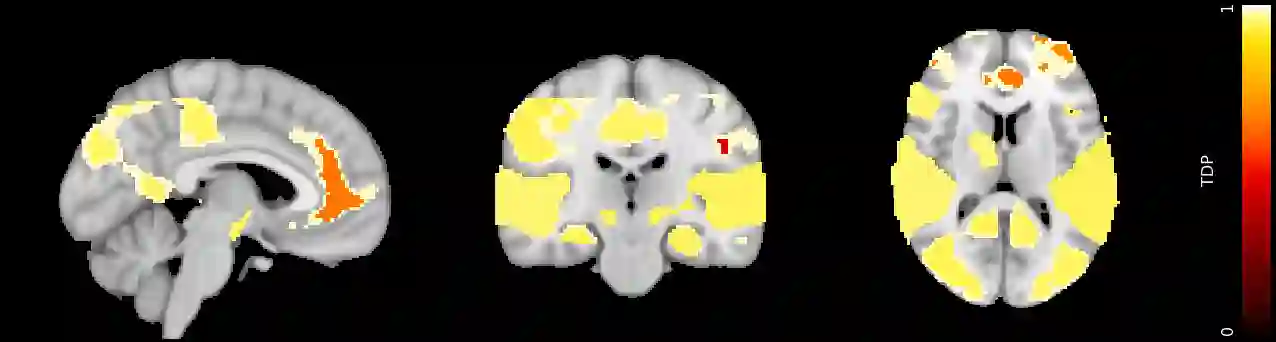

Sum-based global tests are highly popular in multiple hypothesis testing. In this paper we propose a general closed testing procedure for sum tests, which provides lower confidence bounds for the proportion of true discoveries (TDP), simultaneously over all subsets of hypotheses. These simultaneous inferences come for free, i.e., without any adjustment of the alpha-level, whenever a global test is used. Our method allows for an exploratory approach, as simultaneity ensures control of the TDP even when the subset of interest is selected post hoc. It adapts to the unknown joint distribution of the data through permutation testing. Any sum test may be employed, depending on the desired power properties. We present an iterative shortcut for the closed testing procedure, based on the branch and bound algorithm, which converges to the full closed testing results, often after few iterations; even if it is stopped early, it controls the TDP. We compare the properties of different choices for the sum test through simulations, then we illustrate the feasibility of the method for high dimensional data on brain imaging and genomics data.